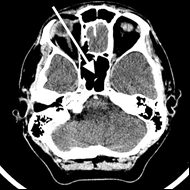

Na radiogramie TK głowy strzałką wskazano

A. zatokę sitową.

B. zbiornik wielki.

C. zatokę klinową.

D. przegrodę nosową.